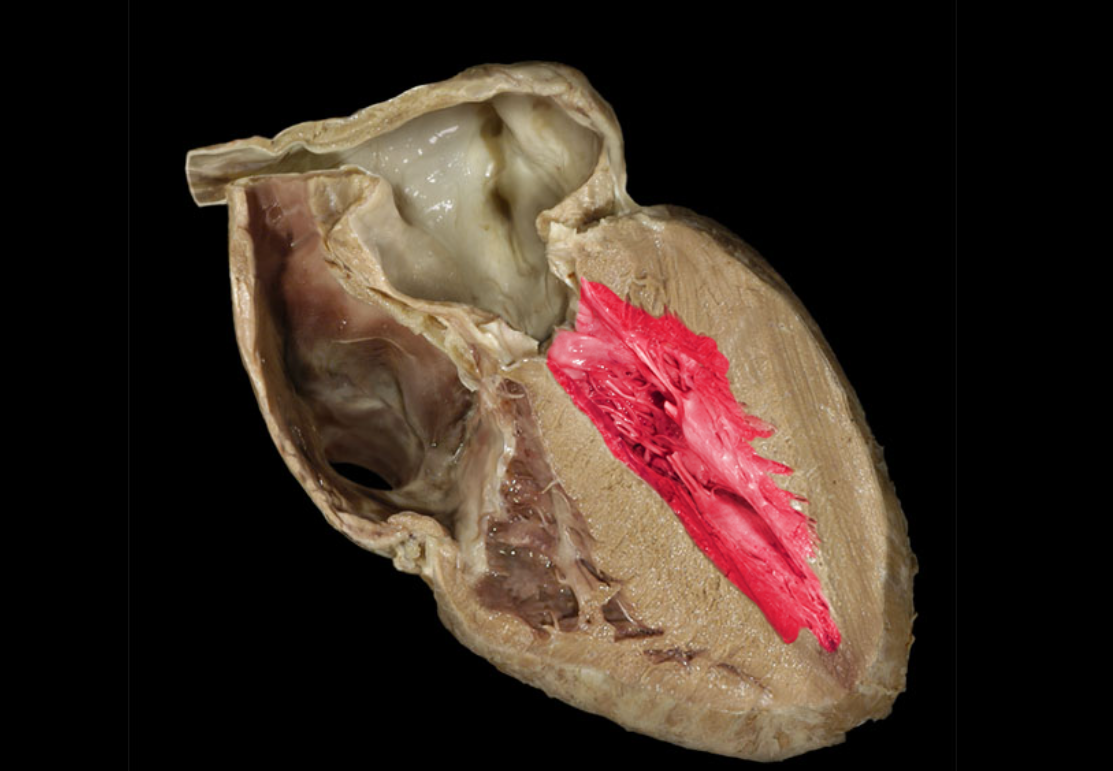

Aortic valve

Ascending aorta

Chordae tendineae

Left atrioventricular valve

Left ventricle

Myocardium of left ventricle

Myocardium of right ventricle

Pulmonary valve

Right atrioventricular valve

Right ventricle